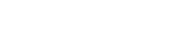

Preoperative AP and Lateral Views

As the patient was wheeled into the operating room, the lead surgeon faced an exceptionally challenging procedure:

Challenge 01:

The patient was only 5 years old, with a small skeletal structure and narrow pedicle channels, along with hemivertebra malformations. To avoid irreversible spinal cord injury caused by repeated punctures, surgeons had to place each pedicle screw correctly on the first attempt, with no room for adjustments. The percutaneous approach presented extreme technical difficulty, making screw insertion comparable to navigating blindly.